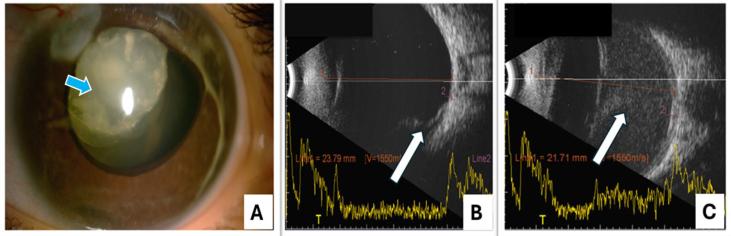

All 36 eyes of the 18 children with biallelic variants exhibited megalocornea without Descemet break, iridodonesis, and ectopia lentis. Pupillary changes were noted in all eyes, with persistent pupillary membrane in 78% (28/36) and ectropion uveae in 19% (7/36) eyes. Secondary glaucoma was observed in 72% (26/36) eyes, requiring surgery in 13 of these. Retinal pathology was noted in 47% (17/36) eyes. Lensectomy was performed in 94% (34/36) eyes with a mean age of 4.09 ± 3.5 years. Logistic regression analysis suggested that older age at lensectomy increased the risk of secondary glaucoma (hazard ratio, 1.69; [95% Confidence Interval: 1.00, 2.86], < 0.05). The identified variants included five stop-gain variations, six frameshift variations, and one substitution variation, with five being novel and seven classified as rare variants.

The study expands the classic -related phenotype spectrum in an Indian pediatric glaucoma cohort, highlighting additional features such as persistent pupillary membrane, ectropion uveae, and associated retinal pathology. These ocular manifestations were predominantly linked to nonsense variants. From a management standpoint, early lensectomy can help prevent secondary glaucoma, while timely identification and treatment of peripheral retinal pathology can reduce the risk of sight-threatening complications.